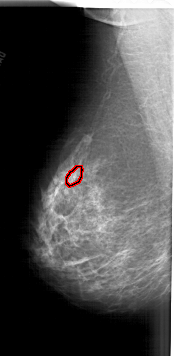

FILE: A_1905_1.LEFT_MLO.OVERLAY

TOTAL_ABNORMALITIES 1

ABNORMALITY 1

LESION_TYPE CALCIFICATION TYPE PLEOMORPHIC DISTRIBUTION CLUSTERED

ASSESSMENT 4

SUBTLETY 3

PATHOLOGY MALIGNANT

TOTAL_OUTLINES 1

BOUNDARY